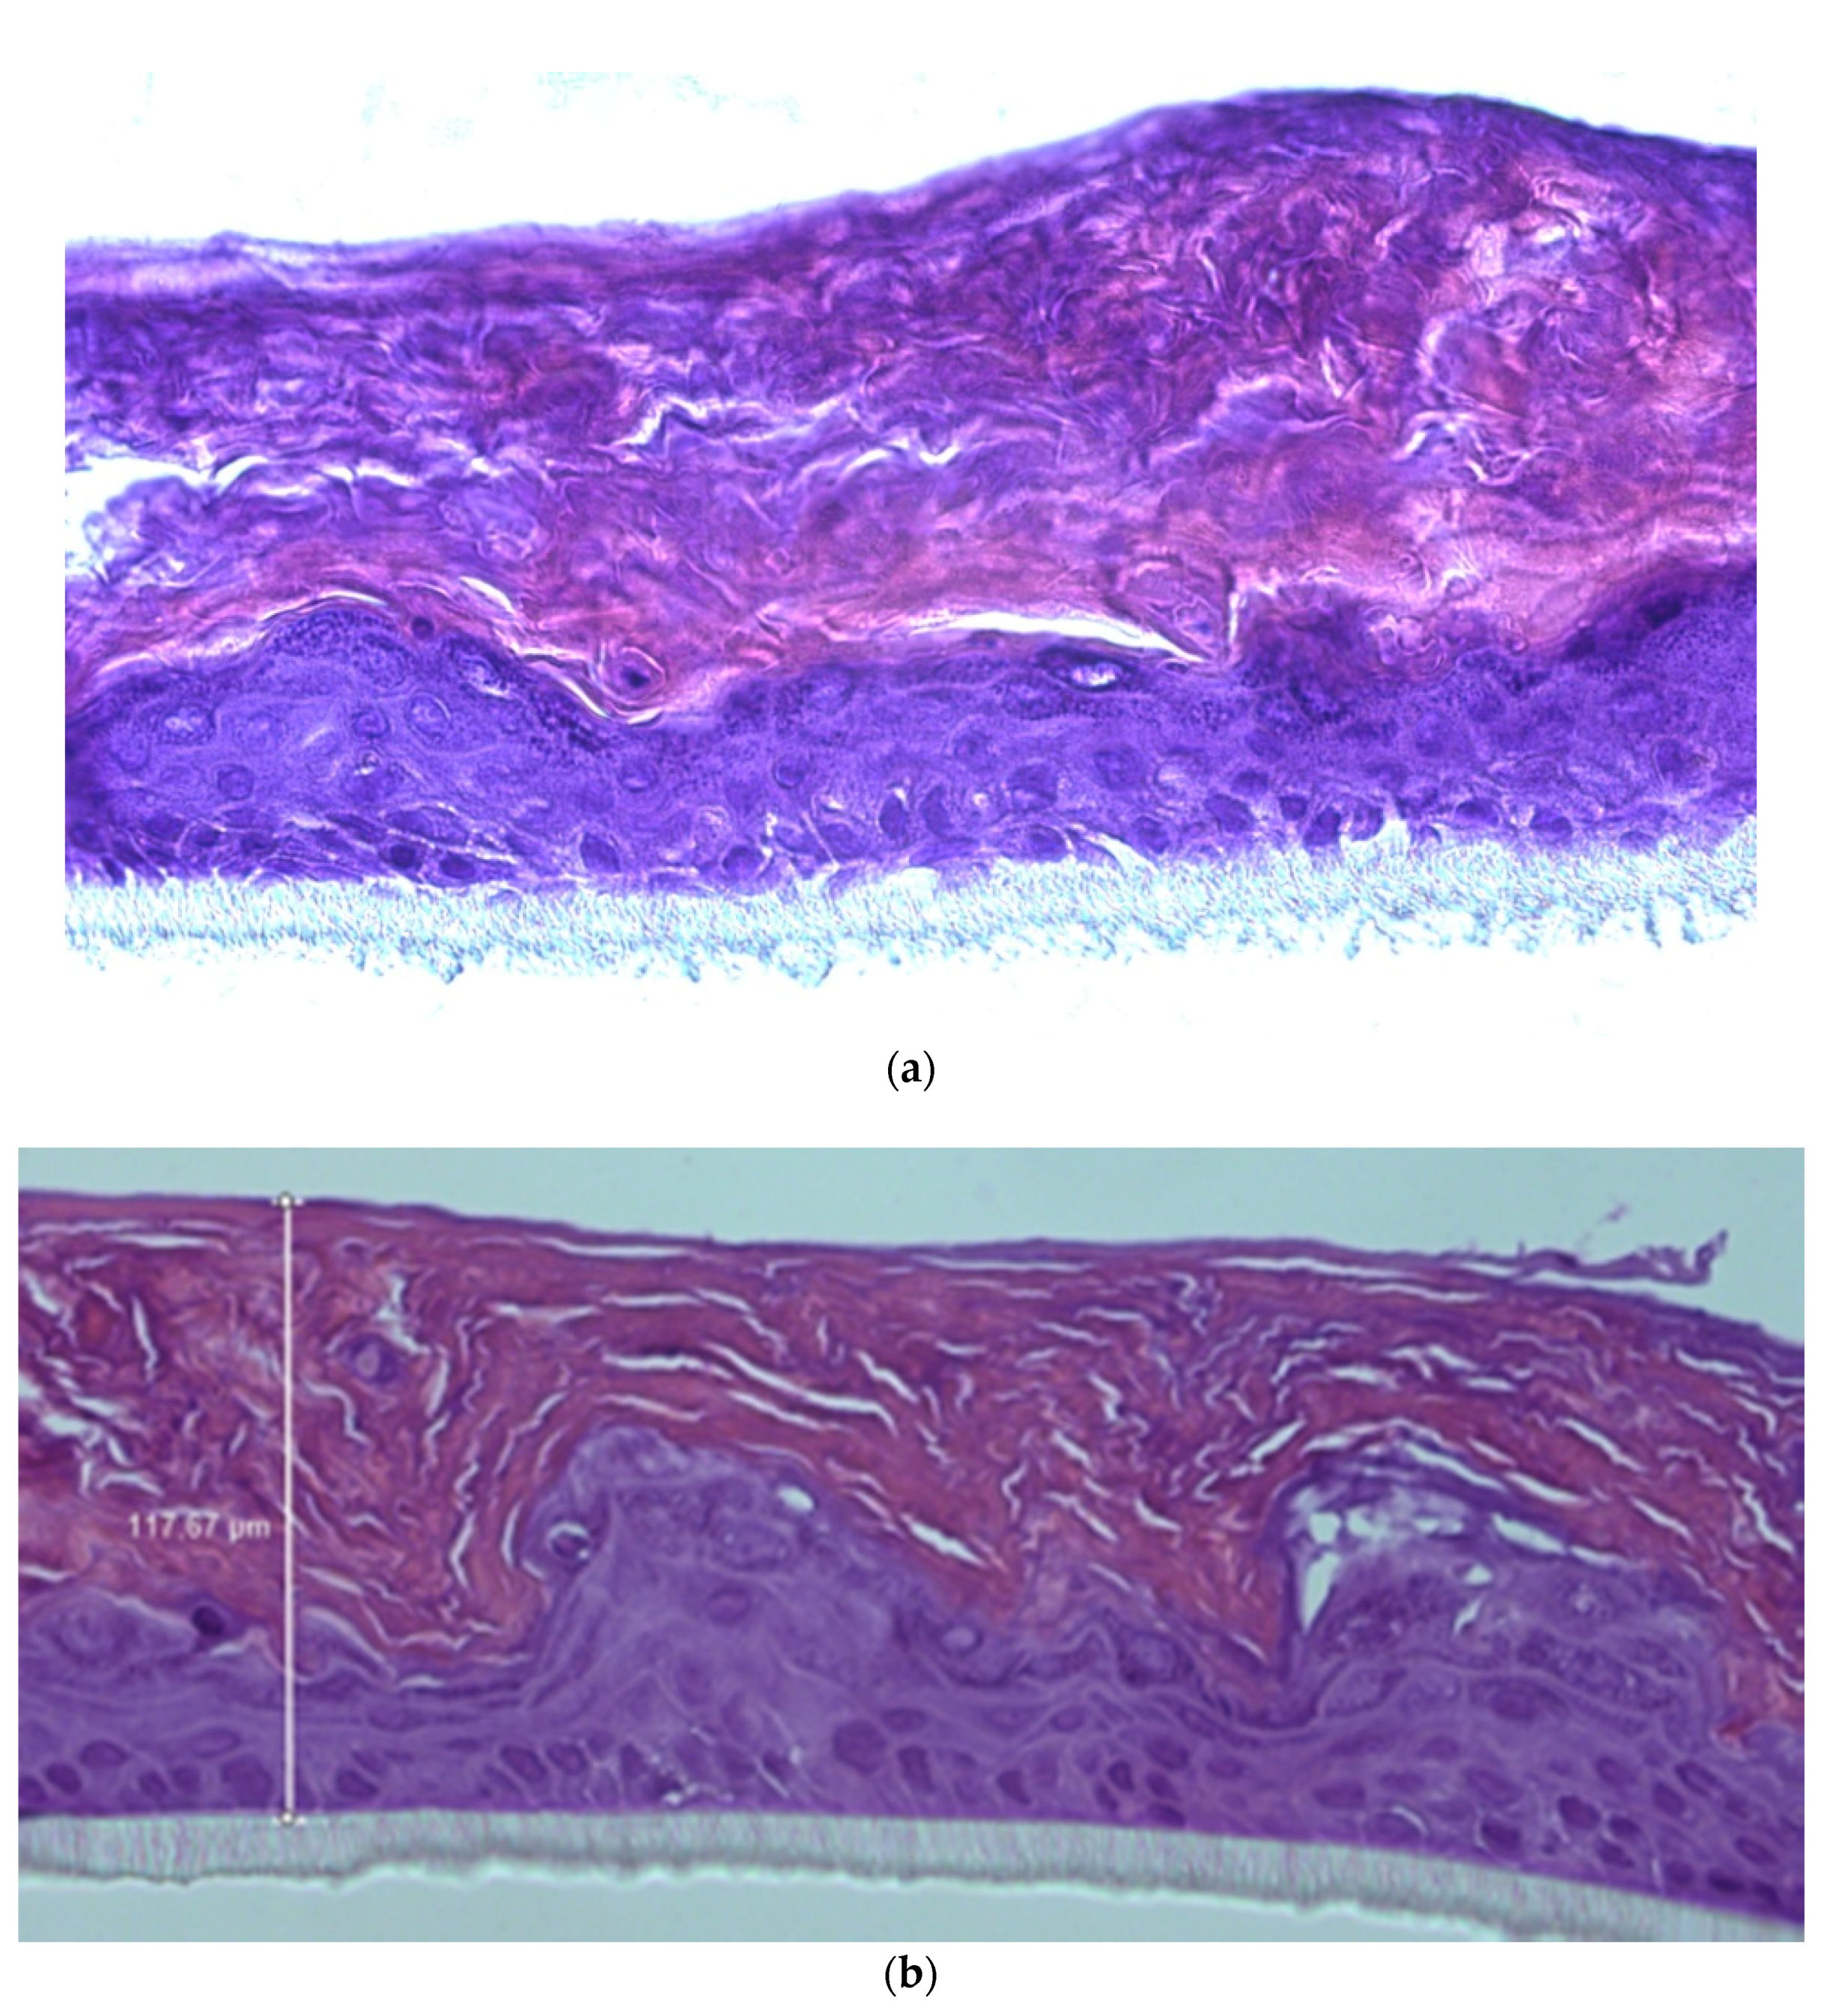

3.2. Re-Epithelizing Efficacy on RHE with Impaired Barrier Function